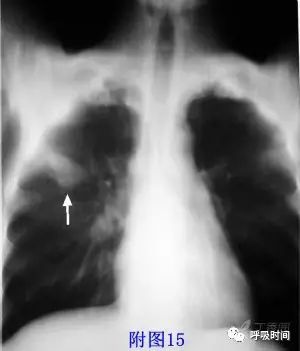

图 15 结节影——手术病理为肺腺癌

图片